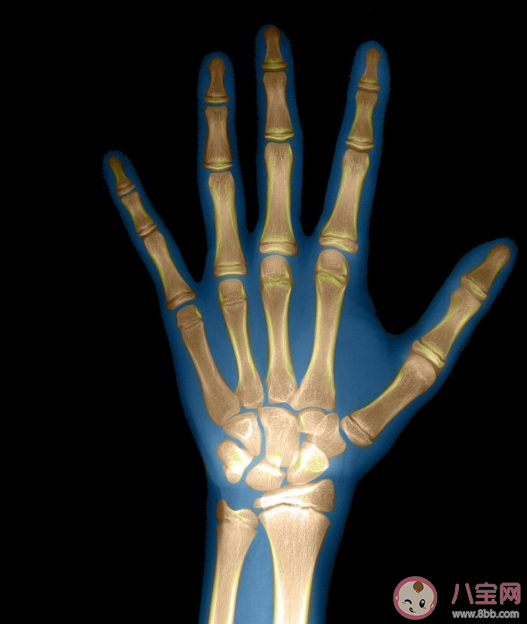

骨骼是反映骨骼生長情況與人體發育程度的重要指標。骨齡,從字面理解就是骨骼的年齡,其實就是兒童骨骼實際發育程度與標準發育程度比較的結果。骨齡是由X光來確定的,一般情況下會拍攝左手腕處,通過對手掌指骨、腕骨與橈尺骨下端骨化中心的發育情況進行觀察最終確定骨齡。